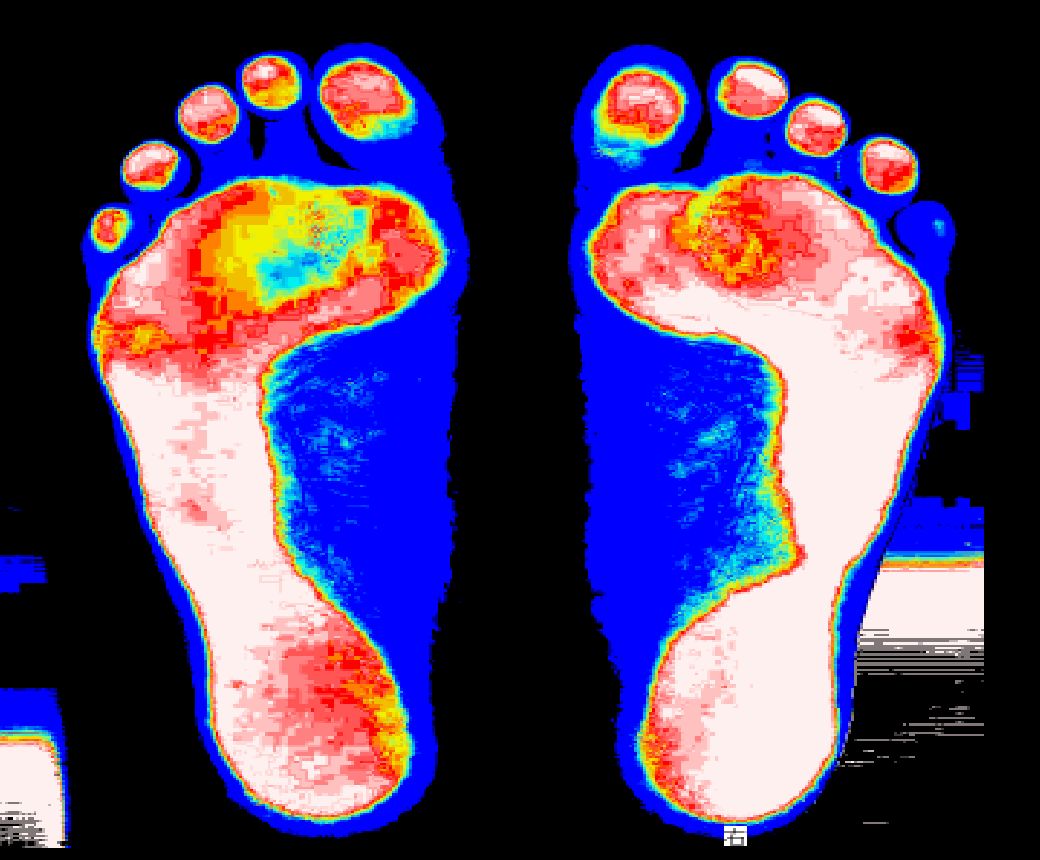

Before

身体に問題を抱えてる人は足の一部分でしか支えていません。

After

コロコロさんを転がす事で足全体で支える事ができます。

(足底圧画像)